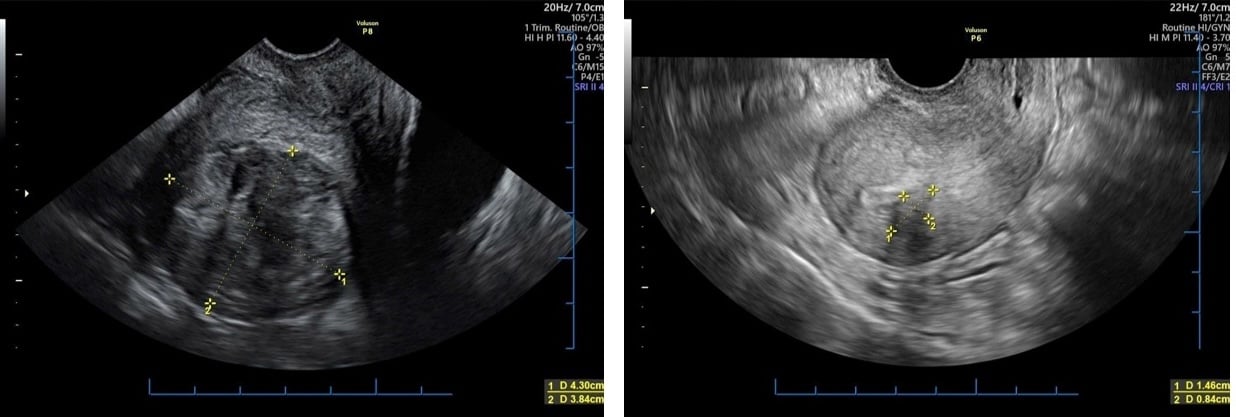

Uterusmyome, vor (linkes Foto) und nach der Behandlung mit US-HIFU

FOTO: BSCC